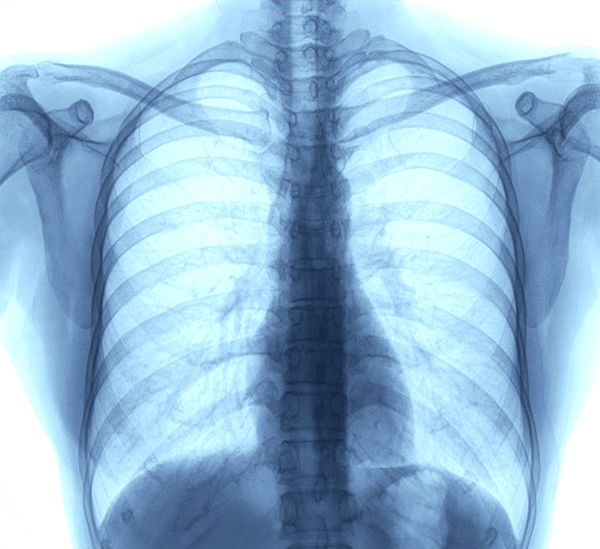

ニューストップ > からだニュース > 禁煙普及も肺がん死亡数はトップ 非喫煙者や女性に罹患者増加も 病気 喫煙 タバコ 文春オンライン 禁煙普及も肺がん死亡数はトップ 非喫煙者や女性に罹患者増加も 2026年3月1日 11時0分 リンクをコピーする 〈5年生存率は約10%「危険性は一目瞭然」膵臓がん…“危険因子”を老年科専門医が解説《最大の防衛術は0期の超早期発見》〉から続く世界で最も多くの患者を有する肺がん。「タバコを吸う男性が罹るものでしょう?」そんな常識も今は昔。肺がんは、非喫煙者の女性たちの間で増加中なのだ。女性の肺がんの知られざる原因とその対策を徹底解説する!(初出:「週刊文春 電子版」2025年12月11日号配信)【写真】この記事の 記事を読む